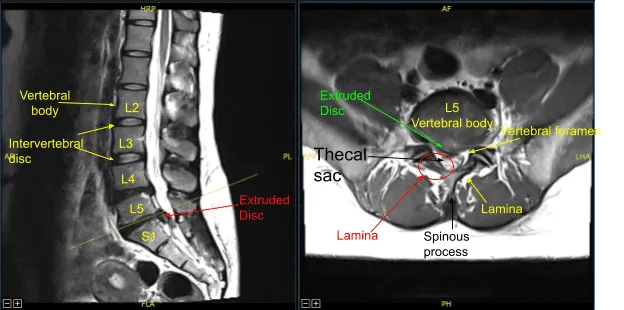

El paciente presentó signos y síntomas de debilidad en la extremidad inferior derecha con una hernia discal intervertebral muy grande en L5-S1 en la resonancia magnética que causó una compresión severa del saco tecal y de la raíz nerviosa S1 del lado derecho. Debido al déficit neurológico y al dolor intenso, se recomendó la cirugía para descomprimir la columna lumbar.

La raíz nerviosa derecha S1 parecía extendida bajo presión e inflamada. Había una hernia discal evidente en la axila entre el saco tecal y la raíz nerviosa S1 derecha.